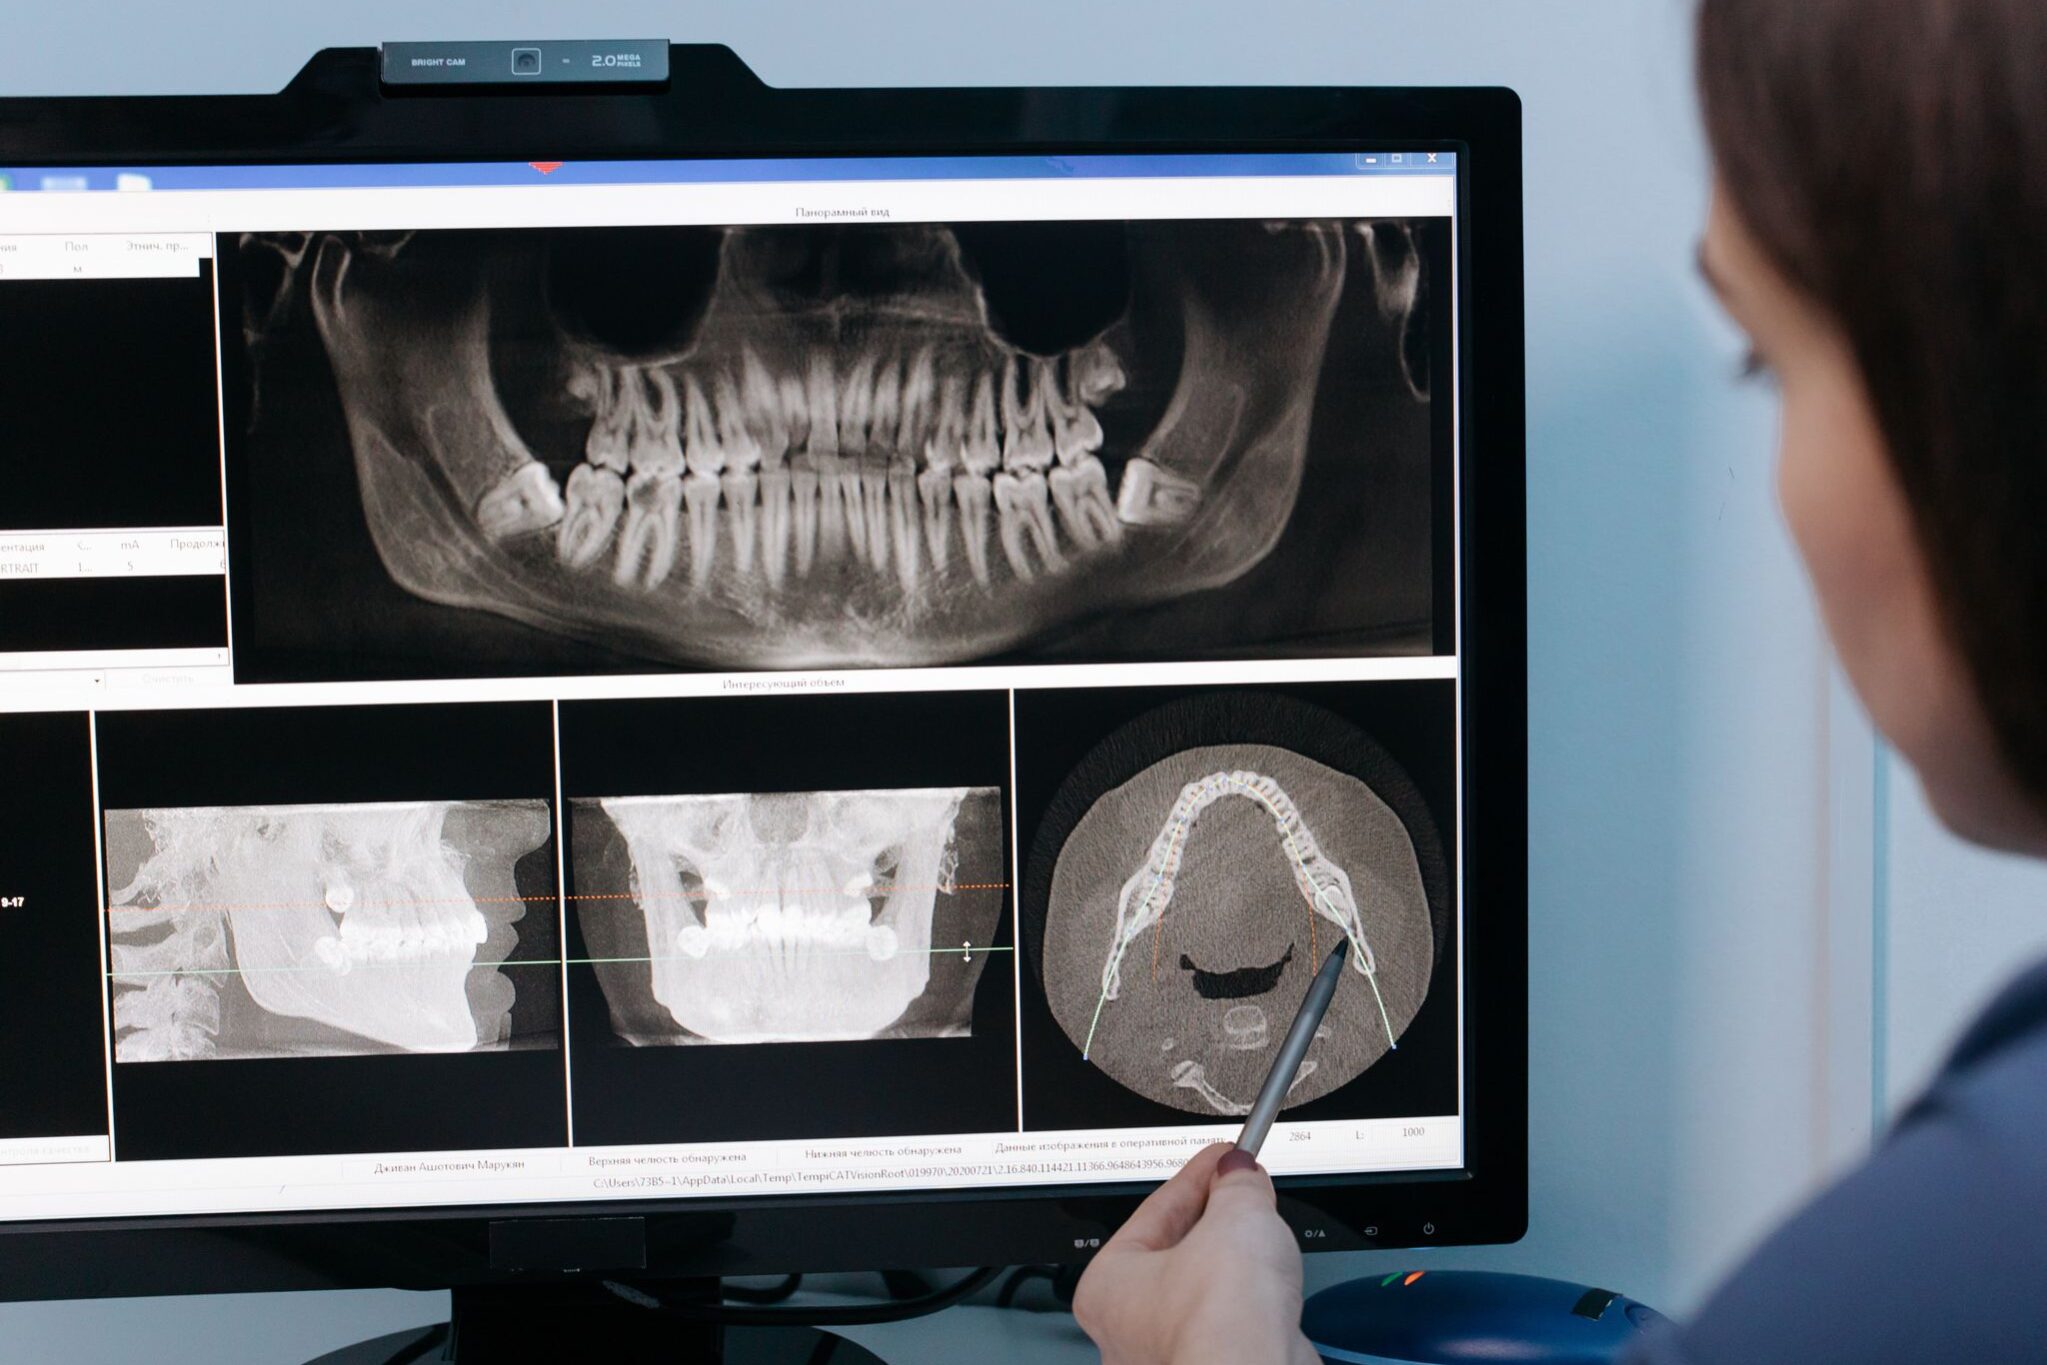

Recomendación: En González y Casado sugerimos realizar una radiografía panorámica anual a partir de los 16 años para evaluar la posición y el desarrollo de las muelas del juicio y decidir si es conveniente extraerlas.

- Realizamos una radiografía panorámica y un CBCT para planificar la extracción de manera precisa.